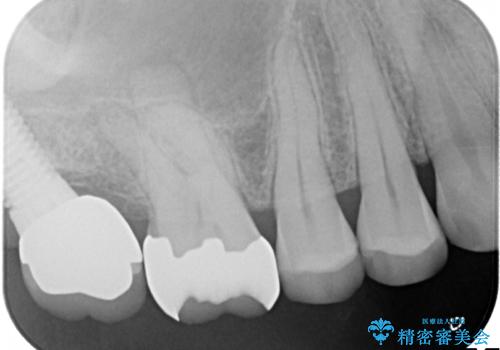

- 古い詰め物を除去し、腐ってしまった神経を顕微鏡下で丁寧に処理する

→根管治療完了後、土台を築造し、かぶせ物を製作してかみ合わせを回復する

すでに感染が根の先端まで及んでいたため、かなり強い痛みがありましたが、丁寧に根管治療をすることで内部を可及的に無菌化し、痛みが消失しました。